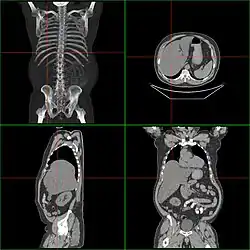

Die zuverlässige Diagnose einer Hepatomegalie ist schwierig, da eine Messung der Lebergröße aufgrund der Variabilität der Leberform nicht gerecht wird. Besser ist die Beurteilung der Leberform, da bei rascher Lebervergrößerung der Leberunterrand stumpfer wird. Des Weiteren kann der Winkel zwischen der ventralen und der dorsokaudalen Leberfläche im Sagittalschnitt gemessen werden. Bei Hepatomegalie beträgt der Winkel mehr als 45°.[1] Ausgeschlossen werden muss außerdem die Pseudo-Hepatomegalie, die etwa bei obstruktiver Lungenkrankheit auftreten kann.[2]